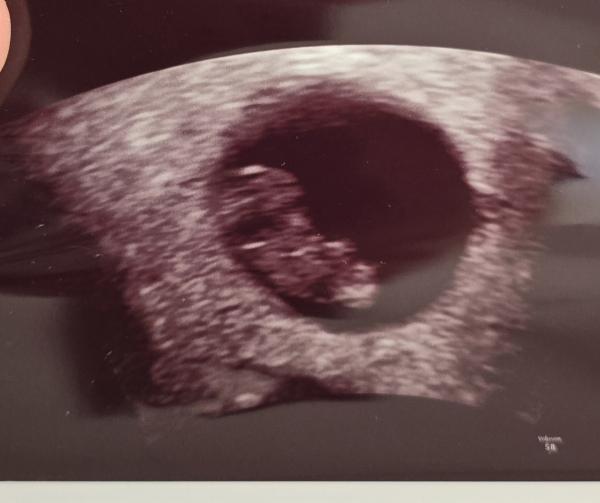

Huhu liebe Letti, ich gucke auch immer mal gerne in die anderen Gruppen rein 🤭 Deine Bilder muss ich wirklich sagen sind sehr schwierig. Würde aber einen Hauch mehr zum Jungen tendieren. Beim Mittleren ist über dem sticht noch ein kleiner kurzer Strich, den haben die Mädels nicht. Ebenso fehlt diese typische Mädchen gabelung vorne. Und bin mir nicht ganz sicher, ob der obere Strich bei (ich glaube bei dem letzten Bild war es) ein ganz kleines mini bisschen mehr nach oben geht. Ich kann es mir aber auch einbilden. Ich muss ehrlich sagen, dass ich die Nub Theorie unfassbar spannend ist und am liebsten den ganzen Tag so Bilder angucken könnte und neugierig bin, was es letztendlich dann ist 🤭

Oh, ich bin ja ganz bei dir. Finde das auch total spannend. Auch wenn das natürlich keine 100% Garantie gibt. Ich muss gestehen, dass ich mich danach ein wenig reingelesen habe und das Ganze trotzdem nicht 100% verstanden habe 🤔😃 Meine Bilder sind aber auch nicht so eindeutig, wie die, die man im Internet (meist) findet. Gerade beim letzten Bild hätte ich eher auf ein Mädchen getippt, weil das für mich so parallel aussah, wo ich eingekreist habe 🥰 Der weiße "Strich/Fleck" oberhalb von dem orangenen Kreis gehört zum Bein. 🤭 Einfach spannend 😍

Ich find es halt interessant, weil die Ärztin bei der Feindiagnostik auch damit anfing und das nochmal erklärt hatte. Schade, dass man den Nub nicht so genau erkennen kann. Oder man kann ihn sehen aber unser ungeschultes Auge bekommt es nicht gebacken 😂 Ich weiß was du meinst. Hab dein Bild frecher weise einfach mal "bemalt" um zu zeigen, was ich meine.

Genau. Das letzte Bild war es. Der untere Strich geht nach unten, der obere nach oben. Es sind nicht beide Parallel verlaufend nach unten.